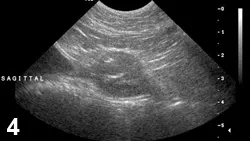

FIGURE 3

Prostatitis with abscess. Sagittal view of an intact canine prostate (cursors); a hypoechoic nodule is visible within the parenchyma. The parenchymal echo texture is mixed.

• Ultrasonographic findings are nonspecific but typically will be of mixed echotexture with hyperechoic areas reflecting fibrosis (Figure 3).